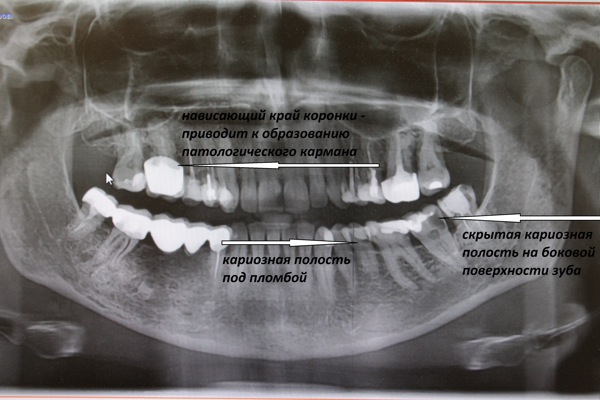

Примеры ортопантомограмм и их анатомия

Раздел: Фотоэссе